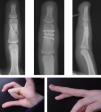

Para llevar a cabo esta técnica se realizó una selección según las características de los pacientes y el tipo de fractura. Es imprescindible que sean pacientes colaboradores y las fracturas subsidiarias de este tipo de tratamiento fueron fracturas inestables que permitían conseguir una buena estabilidad mediante la osteosíntesis con tornillos, como fracturas condíleas de las falanges, fracturas diafisarias espiroideas u oblicuas largas de la falange, fracturas de la base de la falange, fracturas intraarticulares y algunas fracturas de la base del primer metacarpiano (figura 1,figura 2,figura 3,figura 4).

Figura 1. Fractura oblicua larga extraarticular de la falange media del dedo medio.

Figura 2. Fractura de la base de la falange media del dedo anular.

Figura 3. Fractura de cóndilo de la falange proximal del dedo índice.

Figura 4. Fractura de la base del primer metacarpiano.